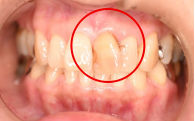

女性 Mさん 40代 (オールセラミック冠)

主訴

上の前歯が欠けた。

治療内容

神経をとる治療をし、根管治療後、ファイバーコアを入れ、オールセラミック冠を被せました。

所感

右前歯がむし歯で大きくかけていました。レントゲンを撮り詳しく診てみると、むし歯が深く、神経をとる治療が必要なことがわかりました。被せ物は、メタルフリーの治療を希望されましたので、ファイバーコアを入れオールセラミック冠を被せました。右上にむし歯があります。今後、そこの部分に取り組んでいきます。

オールセラミック冠1本:¥104,500(税込)

Before

むし歯が深く、神経に到達するむし歯でしたので、根管治療をしました。

After

根管治療終了後